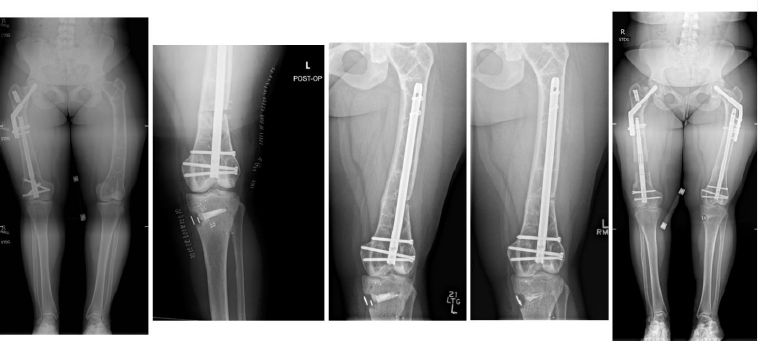

Complications occurred in 5 patients with tibial DC, including 3 cases of hardware removal due to symptomatic prominent interlocking screws and 1 case of delayed union. Complications arose in 4 patients with femoral DC, including 3 cases of nonunion, 1 case of hardware removal due to prominent screws, and 1 case of nonunion and infection (Table 1). There were no cases of peroneal nerve palsy or compartment syndrome. All patients achieved eventual clinical and radiographic union. Pre- and postoperative radiographs of 4 cases are included to highlight the variation in presentation and operative site (Figs. 4-7).

From left to right: Preoperatively, immediately postoperatively, 5 months postoperatively, and 4 years postoperatively (patient #6).

From left to right: Preoperatively, immediately postoperatively, and 4 years postoperatively (patient #4).